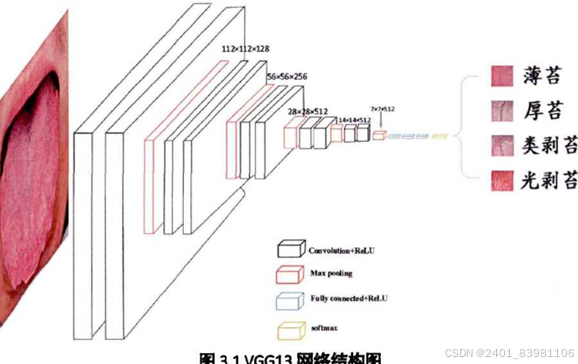

采用VGGNET,GradCAM(可以对任意结构的CNN进行可视化),基于创新h-Net模型的中医舌苔苔质分类及其舌苔特征可视化,基于高光谱图像的中医舌苔和舌质分类等

采用VGG时网络优化过程中应用了Dropout策略网络优化策避免过拟合问题但训练样本较少,采集数据困难,训练样本包含舌头外的无关区域等原因,产生的可视化效果并不够完美,仍具有相当大的改进空间

一篇论文提出的方法实现:

步骤1 .:数据获取并对数据进行编码、归一化处理形成待检测数据,并制作包含训 练集与验证集的数据集。1 .1使用PH试纸或者标准比色卡放置于舌头旁边,以提供标准参考系1 .2使用相机或者手机等拍摄设备拍摄舌头与PH试纸或标准比色卡的照片,保存, 将已确定的标准化舌苔类别图像人工分类分别放入对应的目录中。 1 .3数据编码,将1 .1中获取的数据类别标签进行one-hot编码,健康舌苔图像、不 健康舌苔图像分别对应01 ,10两位二进制数。步骤2:利用Keras搭建深度卷积神经网络。 2 .1使用基于tensorflow的Keras,调用其内置函数,搭建一个CNN2D的网络,激活 函数使用relu。2 .2在2 .1的基础上,向其添加一层最大池化层。2 .3反复2 .1-2 .2操作,添加若干组CNN2D与最大池化层。2 .4在2 .3的基础上,向其添加一层平坦层。2 .5在2 .4的基础上,向其添加一层全连接层,激活函数使用relu。2 .6反复2 .5,向其添加若干层全连接层。2 .7在2 .6基础上,向其添加输出层,2个神经节点,激活函数使用softmax,完成网 络搭建。步骤3:将步骤1所划分的训练数据输入步骤2搭建的神经网络,对神经网络进行训 练。3 .1将步骤1中的到的两类数据混合并对应好其label,输入步骤2得到的网络中, 其中数据总量的80%用于训练,10%用于验证,10%用于测试。3 .2训练若干个epoch后,验证准确率不再上升,即停止训练,用测试集测试其准确 度。3 .3反复调参,直到得到最优模型。 步骤4:深度学习模型训练完成后保存权重参数,并利用该权重对测试数据进行识别分类。4 .1保存权重与模型结构,对用户数据进行预测。